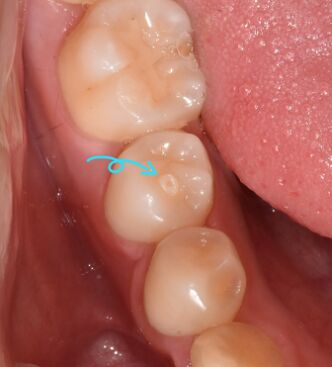

1.下圖所標示處,那個診斷是正確的? (A)卡拉貝利咬頭(cusp of Carabelli)(B)爪形咬頭(talon cusp)(C)齒中齒(dens in dente)(D)齒外齒(dens evaginatus)